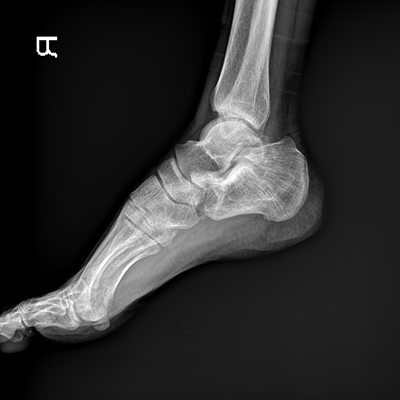

●探測器可以大范圍轉(zhuǎn)動,大尺寸有效探測面積,可滿足人體多部位攝影需求。